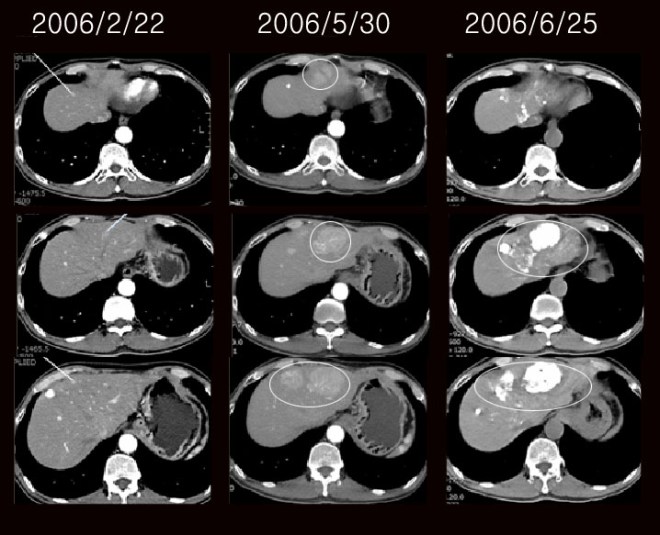

이 환자는 한 달여 동안 짜고 맵게 먹었다. 워낙 꼼꼼한 소음인 성격이라 나름대로 철저히 하고 라파뮨도 끊었다. 다음은 이후 8월달에 가지고 온 사진이다.

이 환자는 소음인 중에서 조금 의심이 많고 자신의 계획을 철저히 실행하는 성격으로 보였다. 나의 지도를 받고 이렇게 좋아졌는데도 한약에 대한 불신은 여전하여서 한방치료를 받지는 않았다. 그래서 그 뒤 결과에 대해서는 자세히 알 수가 없지만 이 사례를 비추어 볼 때 아무리 약이 받아도 체력이 안 되고 흡수력이 떨어지면 항암제가 작용할 수 없다는 것을 이야기해 둔다. 또한 기존의 암에 대한 생각은, 암을 예방하거나 암을 치료하는 분들이 간암에는 짜게 먹지 마라고 당부하는데 이는 크게 잘못된 생각이다. 섬유화나 지방이 쌓이는 것도 역시 Na +이 이를 억제할 수 있다. 싱겁게 먹음으로써 장내에서 지방의 흡수를 재촉하게 되고 혈중에서 지방의 분해를 억제하게 된다. 이 환자는 한약을 먹은 것이 아니고 단지 소음인에게 맞는 식이요법과 음식을 짜게 먹음으로써 무섭게 진행되던 암이 멈추고 거꾸로 줄어들기 시작하였다는 것은 세포들이 그동안 시든 나무 처럼 죽어 있다가 짜게 먹음으로써 물이 돌기 시작하고 나무에 물뿌려진 것처럼 정상적인 반응을 하기 시작하자 암세포가 줄어들게 된 것이다. 그리고 이 환자가 왜 짜게 먹음으로써 다시금 듣지 않던 색전술이 효과를 발휘하게 됐나는 2강에서 설명하려고 한다.